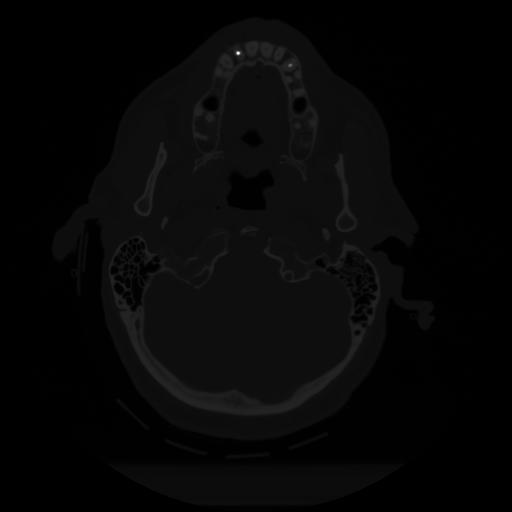

12 P.BLANDAS,,Vol,0.5,P.BLANDAS,,